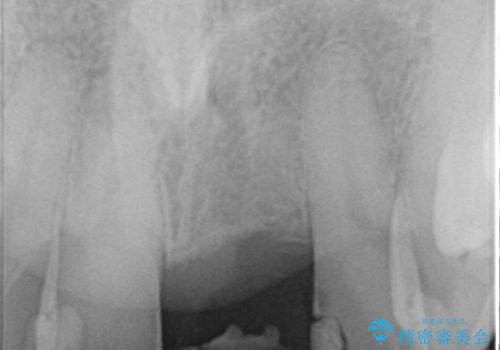

- 以前、前歯にボールが当たりダメになってしまって抜歯したが、そこにとりあえず接着剤で歯をつけて生活していたとのこと。

両側の歯の接着剤の周りが虫歯になってしまっていました。

両側の歯の虫歯をしっかりとってブリッジにすることにしました。

欠損部に長年薄いプラスチックの仮の歯を留めていたため、下の歯が食い込みさらにブリッジのポンティックの隙間がない状態でした。そのため、かみ合わせが深く、下の歯との隙間がかなりなかった為、事前の矯正治療をお勧めしましたが、希望されず特に行わずそのまま虫歯治療を行うことになりました。